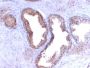

This antibody recognizes a single protein of 33-34 kDa, identified as the prostate specific antigen (PSA). This MAb is highly specific to PSA and stains prostatic secretory and ductal epithelium in both normal and neoplastic tissues. PSA is a chymotrypsin-like serine protease (kallikrein family) exclusively produced by the prostate epithelium, and abundant in seminal fluid. PSA can be detected in the sera of patients with prostatic carcinoma. It is predominantly complexed to a liver-derived serine protease inhibitor, alpha-1-antichymotrypsin (ACT). A higher proportion of serum PSA is complexed to ACT in prostate cancer than in benign prostate hyperplasia. This MAb makes an excellent pair with MAb A67-B/E3 for PSA tests.Primary antibodies are available purified, or with a selection of fluorescent CF® Dyes and other labels. CF® Dyes offer exceptional brightness and photostability. Note: Conjugates of blue fluorescent dyes like CF®405S and CF®405M are not recommended for detecting low abundance targets, because blue dyes have lower fluorescence and can give higher non-specific background than other dye colors.

Positive Control

PC12 cells or normal prostate or prostate carcinoma

IHC (FFPE) (verified)

Higher concentration may be required for direct detection using primary antibody conjugates than for indirect detection with secondary antibody|Immunohistology (formalin): 0.5-1.0 ug/mL for 30 minutes at RT|Staining of formalin-fixed tissues is enhanced by boiling tissue sections in 10 mM Tris with 1 mM EDTA pH 9.0 for 10-20 minutes followed by cooling at RT for 20 minutes|Optimal dilution for a specific application should be determined by user